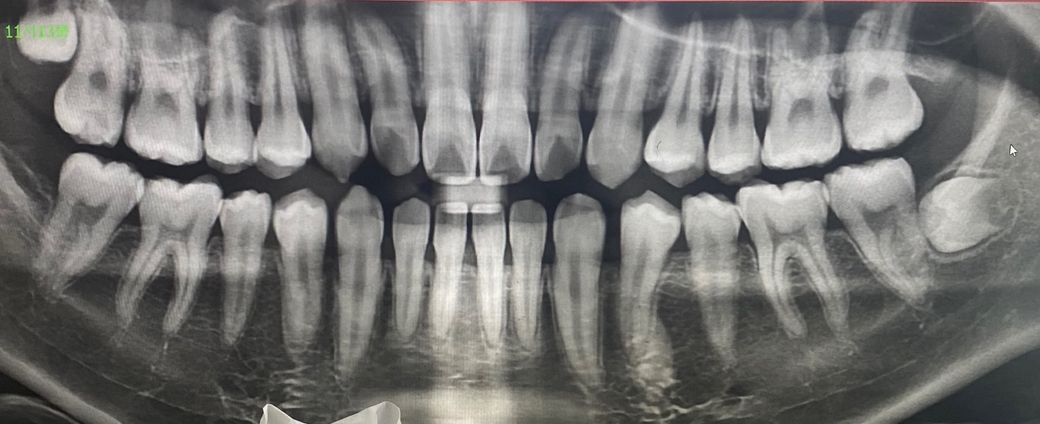

엑스레이로 신경 치료까지 해야하는 상황인지 판단 부탁드려요

사진상 왼쪽 맨 끝 윗어금니가 충치입니다.

신경 치료를 해야 할 거 같다고 진단을 받았는데 충치가 실제로 신경까지 진행된 상황인가요?

파노라마 상으로 안쪽에 충치가 깊은것 같습니다. 큰 사진보다는 정확하게 보기 위해서 작은 사진을 더 찍어보시는게 좋을것같습니다.

충치가 큰 편이기 때문에 신경치료 가능성도 있어보입니다. 충치의. 진행정도는 심한 편입니다.

오른쪽 위에 7번째 어금니에 교환면으로 충치가 보이고 있습니다. 사진으로 봤을 경우에는 신경까지 진행이 되지 않은 것으로 생각되나? 실제적으로 충치를 제거하면 더 깊게 있을 가능성도 있습니다. 신경 신경 치료의 가능성은 사진으로만 판단을 할 수 있는 것이 아니라 충치를 제거하는 과정과 치아 내부의 신경관의 크기에 따라서 달라지게 됩니다.

자세한 확인을 위해서 치과에서 진료를 받아보는 것을 권유드립니다.

엑스레이상 신경이 노출될 정도로 충치가 진행되진 않았으나 원래 충치는 엑스레이로 보는 것보다 더 깊게 진행되었을 경우가 많습니다 그래서 엑스레이만 보고 신경치료 여부를 판단하긴 어렵습니다